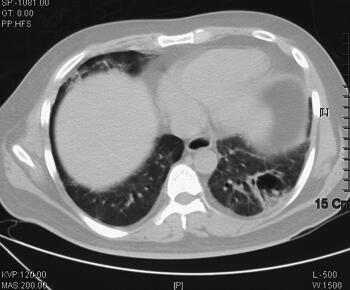

辅助检查:2011年4月5日胸部CT示双肺感染(图1)。血气分析:pH 7.40,PCO2 38.2mmHg,PO2 35.6mmHg,22.9mmol/L,BE −0.7mmol/L,SBE −1.0mmol/L,SaO2 65.0%,提示低氧血症;血常规:WBC 16.8×109/L,Hb 172g/L,PLT 56×109/L,N 0.917;急诊生化:ALT 89IU/L,TBTL 49.0μmol/L,Glu 7.64mmol/L,UREA 14.30mmol/L,CREA 132μmol/L,cTnI 0.04ng/ml。

图1 2011年4月5日胸部CT示双肺感染